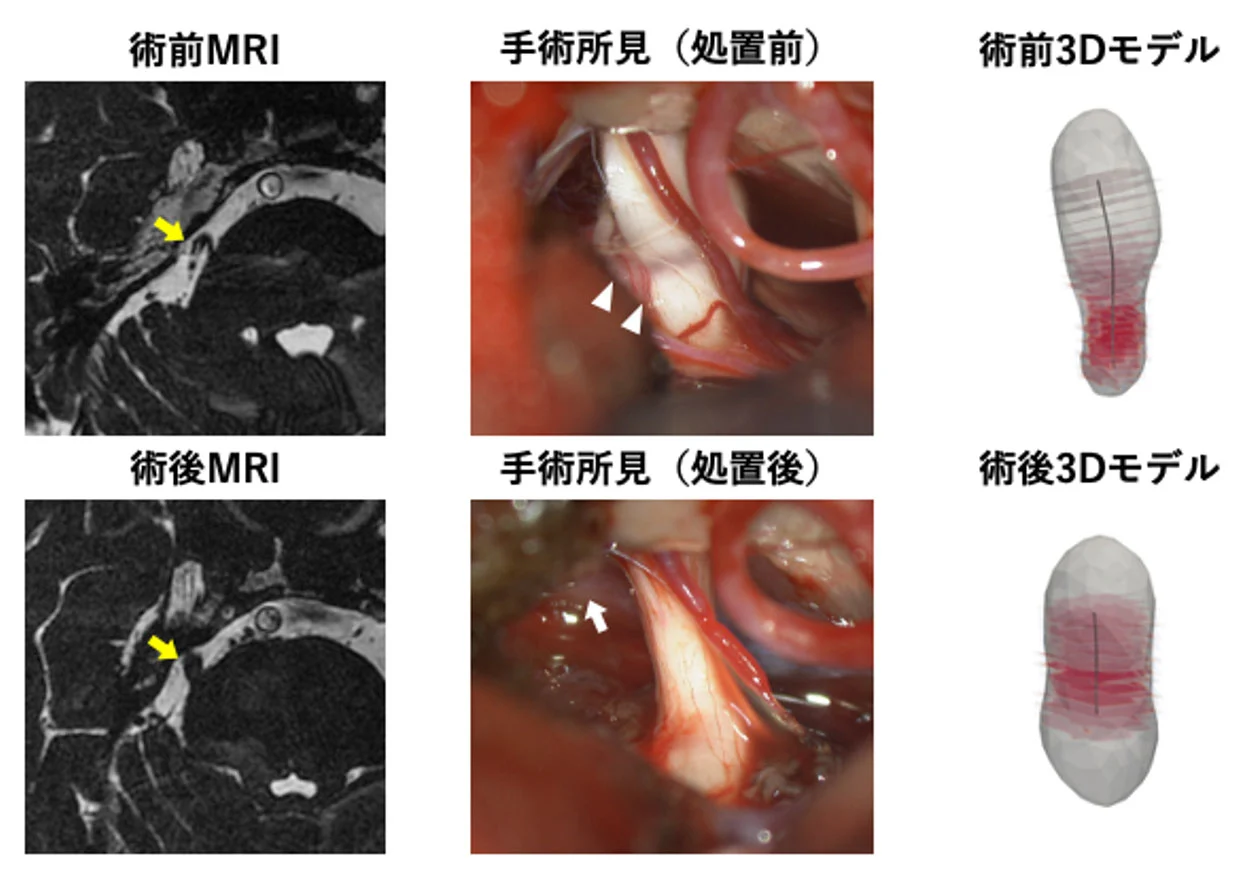

図1. 動脈による圧迫が原因の三叉神経痛の1例。術前MRIにて三叉神経と動脈の接触を認めたため、神経減圧術にて動脈を移動させて圧迫を解除しました。術後MRIでは三叉神経と動脈の接触は消失しました。術後に三叉神経が直線化して太く変化していることが分かります。